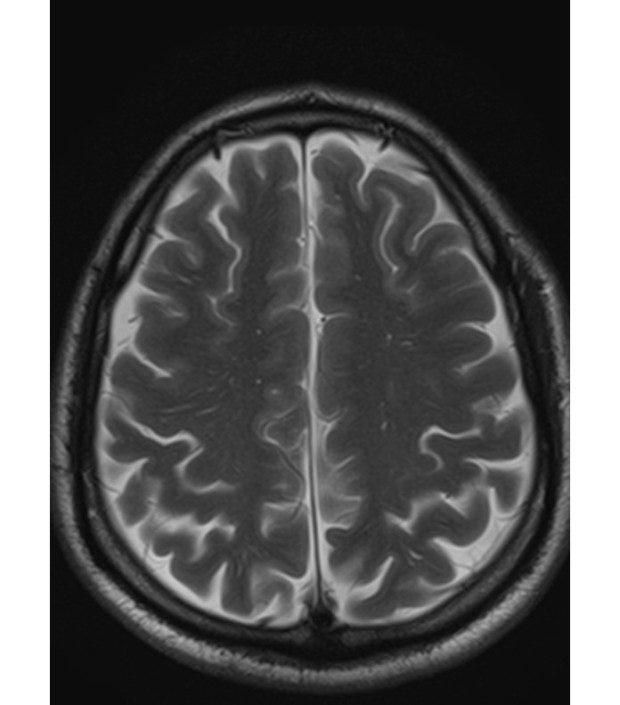

뇌 mri 사진인데 좁쌀같은 부분은 뭔가요 ?

사진 보면 좁쌀같은 하얀 점같은 것이 보이는데... 무슨 병인가요 ? ㅠ 혈압 당뇨 있고 야간에 밤 새는 직업이라 항상 뇌쪽 건강이 걱정되는데...

• 1번 째 사진

뇌MRI를 촬영했는데 뇌실질에 자그만한 하얀점이 많이 있어서 걱정이 되셨군요

말씀하신 뇌실질에 하얀 병변은 소혈관질환이라고 합니다.

약간 과격한 표현을 쓴다면 작은 뇌경색이라고 보시면 될 것 같습니다.

그러니까 동맥경화의 결과로 인하여 작은 혈관에 문제가 생긴 것이지요

• 올려주신 영상은 뇌 T2 강조 영상의 정상적인 대뇌겉질(gyri) 주름 구조가 보이는 형태에 가깝습니다. 질문하신 “좁쌀 같은 하얀 점”은 영상상 뇌겉질의 주름 사이로 보이는 정상 신호거나, 정상 혈관 단면·미세 구조로 보일 가능성이 높습니다.

1. 미세 허혈(약한 혈관성 변화, 작은 백질변성)

– 고혈압·당뇨가 있는 경우 40대 후반~50대부터 서서히 나타날 수 있음

– 아주 초기 단계에서는 작은 점 형태로 보이기도 함

– 대부분 경미한 경우 임상적으로 큰 문제는 없지만, 장기적으로는 관리가 필요함

2. 영상 촬영 특성에 따른 정상 신호 패턴

– 단면 위치·해상도·T2 특성 때문에 좁쌀처럼 보일 수 있음

– 젊은 사람들도 흔히 보입니다

현재 사진 한 장만으로 ‘병변’이라고 단정하기는 어렵습니다.

실제 판독에서는 같은 부위를 다른 시퀀스(T1, FLAIR 등)에서 비교해 미세허혈인지 정상 구조인지 판단합니다.